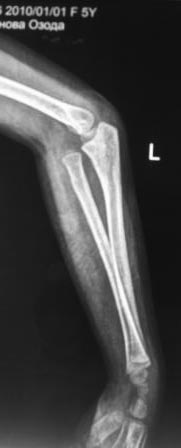

Обратилась девочка 2010г.р., 8 месяцев назад в результате падения на

руку получила травму, гипсовая повязка , которую сняли через неделя и

дальше не лечилась, со слов матери постепенно нарастает деформация.

Объективно отмечается волярное выбухание головки лучевой кости, и

гиперэкстензия в локтевом суставе, функция почти не нарушена, супинация

и пронация сохранены. Какой-то чувство, что возможно была разгибательный

переломо-вывих Монтеджа. Фото руки и Р-снимки представляются.